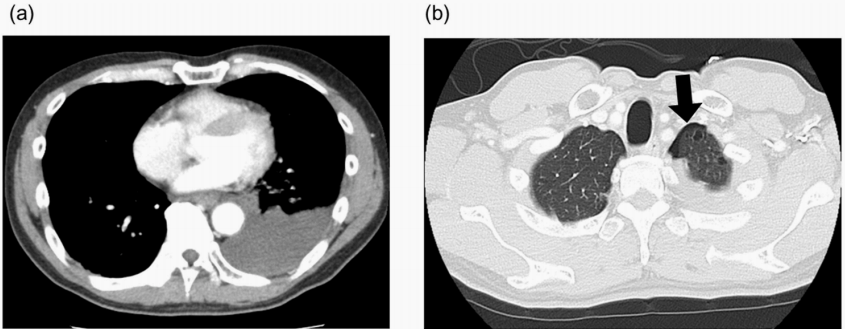

在患者症状发作约1小时后获取的胸部CT图像显示中度胸腔积液

(图1a)和轻度气胸

图1 初诊时胸部CT显示左侧中度胸腔积液(a)和轻度气胸(b)。